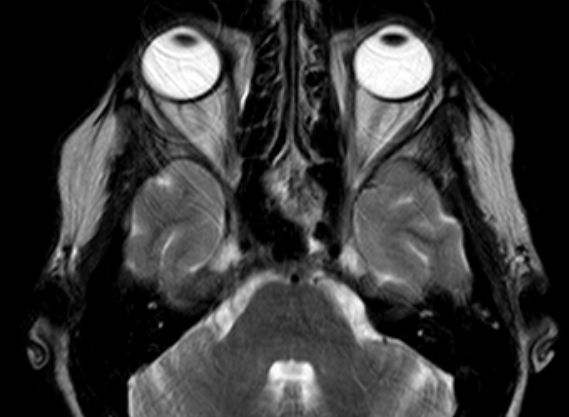

50-jährige Frau (I251), die vor 7 Jahre ein Mammakarzinom (rechts oben außen, T1c No Mo, invasiv NST hatte. Bisher metastasenfrei. Jetzt vor der Sella, in der linken Keilbeinhöhle eine z.T. verkalkte Raumforderung. 2 Jahre unverändert kontrolliert.